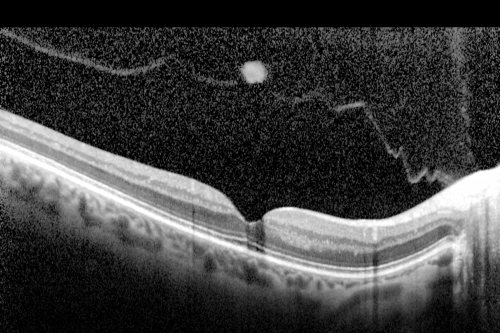

Prefoveal Opercula after Aborted Stage 2 Macular Hole - Present for 1 Year - VA 20/20 - OCT

This pleasant 61-year-old man had a small Stage 2 macular hole, which spontaneously close 12 months ago. He is still bothered by a pre-foveal opercula. OD 20/20.